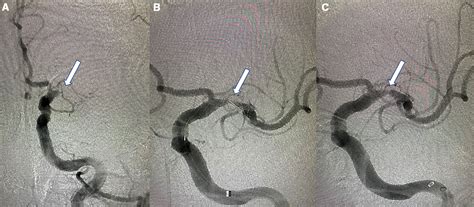

During a mechanical thrombectomy, an interventional neurologist or neurosurgeon inserts a catheter through a large artery (usually in the groin) and navigates it up into the brain. Using specialized devices like stents or aspiration catheters, the physician physically removes the clot. This procedure has revolutionized stroke care, significantly expanding the window of time during which a patient can be successfully treated and potentially regain function.